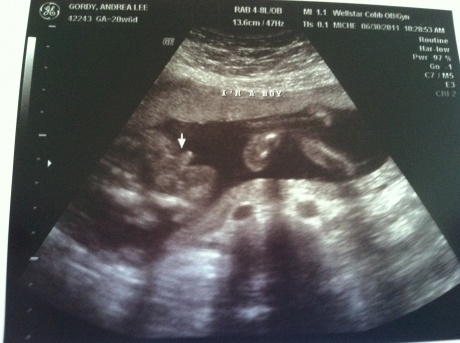

June 30th, 2011- The day we found out we were having a BOY!!!